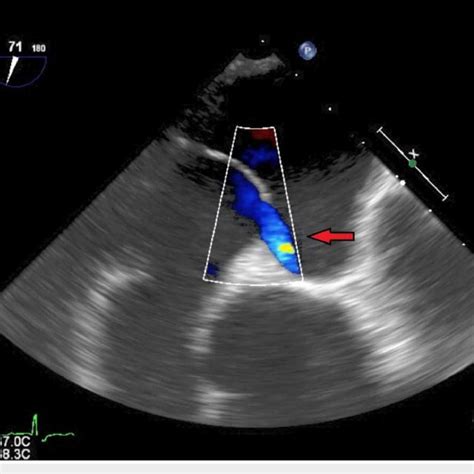

640×640

researchgate.net

TEE-guided PFO device closure. A 40-year-old woma…